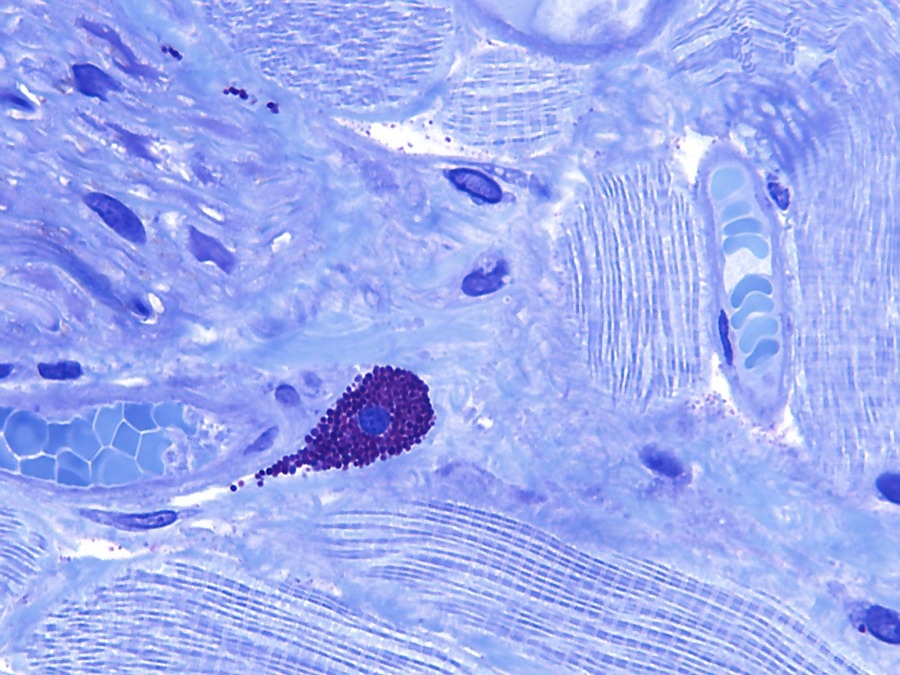

Mestcellen zijn ovale tot ronde cellen met een doorsnede van 20-30µm, waarvan het cytoplasma rijkelijk gevuld is met basofiele granula. De centrale, ronde kern gaat bij bestudering in een lichtmicroscoop vaak schuil achter de granula. In een coupe vervaardigd uit paraffine zijn de afzonderlijke granulaatkorrels en celkern vaak minder goed zichtbaar. In een coupe van kunststof zoals Technovit of Epon is de coupedikte zo gering dat de mestcel meestal wel met granulaat en kern duidelijk zichtbaar kan worden gemaakt. Zie afbeeldingen op de website (Red).

Mestcellen zijn tamelijk lang levende cellen en zijn, in tegenstelling tot de andere vaste bindweefselcellen, waarschijnlijk afkomstig van een stamcel[2] in het beenmerg[2]. De cel komt door het hele lichaam voor, maar vooral in de dermis[2] (rond de bloedvaten), het darmkanaal en de luchtwegen. De cellen kunnen zichtbaar gemaakt worden door een metachromatische kleurreactie[3], waarin toluidineblauw de granula roodachtig purper kleurt, doordat zij gesulfateerde glycosaminoglycanen[2] bevatten.

Mestcellen in een muizen tong preparaat

In de hier getoonde coupes van een muistong zijn geen mestcel ophopingen te zien maar wel zijn de mestcellen in grote hoeveelheden aanwezig. In bijvoorbeeld menselijk weefsel komen veel minder mestcellen voor[Red].

In ‘A practical guide to the histology of the mouse’ is te lezen dat bij knaagdieren deze grote hoeveelheid volledig normaal is en dus geen

ziektebeeld is. Citaat: “Heavily granulated mast cells are commonly seen in normal rodent tongues and can be demonstrated with toluidine blue staining.”[5]